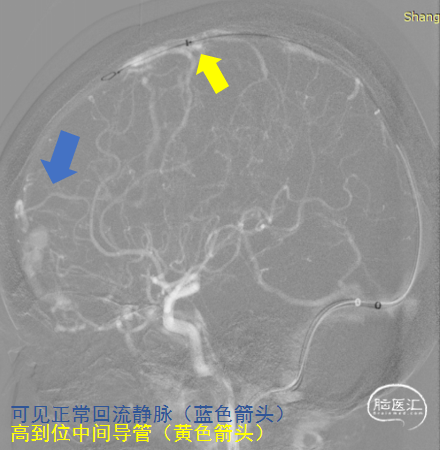

125cm Tethys®中间导引导管利用其远端柔软性,经长鞘高到位后,稳定支撑通路系统。

Echelon微导管经DCwire™微导丝,经过近端扭控,远端克服刁钻“回转弯”后引导微导管顺利进入近端静脉球。后马拉松微导管到达近动脉瘘口。

DCwire™微导丝配合Echelon微导管、通过优秀的扭控到位性及输送性,为微导管顺利到位提供保障。通过Echelon微导管首先稳定栓塞近端静脉球。

2、引流静脉汇入矢状窦前的扩张静脉球近心端存在一支正常回流静脉,栓塞中需要弹簧圈致密栓塞静脉球以确保Onyx充分弥散瘘口,同时又能很好控制Onyx的返流,保护正常引流静脉。